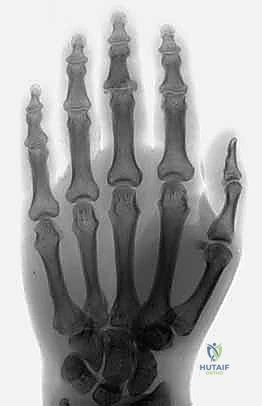

معرض الصور الشعاعية: رحلة الشفاء من الكسر إلى التعافي

لفهم مدى فعالية هذه التقنية، دعونا نستعرض سلسلة من الصور الشعاعية لحالات حقيقية ومعقدة، توضح حالة المفصل قبل التدخل، أثناء الجراحة، وبعد الالتئام التام.